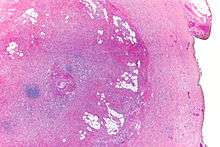

| Micrograph showing a goblet cell carcinoid. H&E stain. | |

Micrograph of a goblet cell carcinoid. H&E stain.

GCCs are diagnosed by pathology. They have a characteristic biphasic appearance which includes (1) goblet cell-like cells, and (2) neuroendocrine-type nuclear chromatin (stippled chromatin).